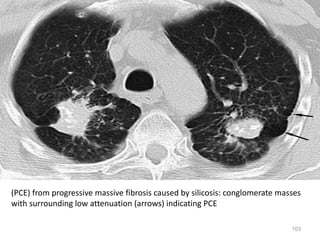

(PCE) from progressive massive fibrosis caused by silicosis: conglomerate masses

with surrounding low attenuation (arrows) indicating PCE